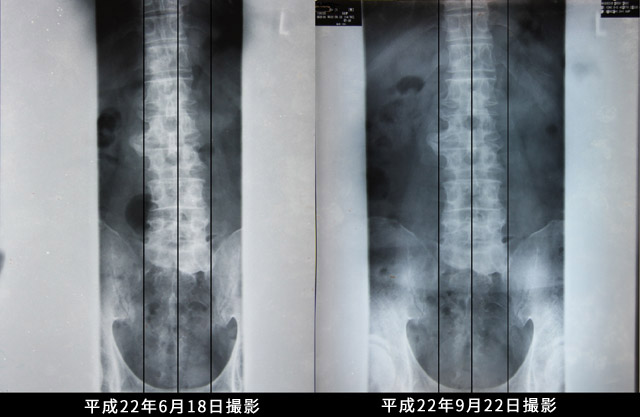

男性 Y.I.さん 59歳 愛知県『腰痛 歩けない 立っていられない』

16歳の時に腰を損ねて以来毎年のようにぎっくり腰を起こすようになりました。 病名は椎間板ヘルニアでした。

6年前に損ねた時はいつも通う接骨院でも回復せず結局激痛で 全く歩くことも起き上がることもできなくなり入院となりました。 ブロック注射は効果なく点滴とリハビリの40日間の入院となりました。 病名はヘルニアと脊柱管狭窄症でした。

今回は2月に腰を痛めて以来歩行に困難をきたすようになりました。

連続歩行は300mぐらいが限界、立つのは5~10分が限界といった具合でした。 もう手術しかないかなと思っている頃、桑名在住の義姉の紹介で当院を知り ホームページを見て一度診てもらう気になりました。 6月~7月は毎週片道125km3時間半かけて桑名に通いました。 施術のたびに効果を出すとの先生の言葉どおり 回をかさねる毎に歩行距離が伸び盆過ぎには2Kmのジョギングができるようにまでなりました。 12月現在症状は全く表われずウォーキングも平均15000歩で快適に過ごしております。 先生に本当に感謝しています。